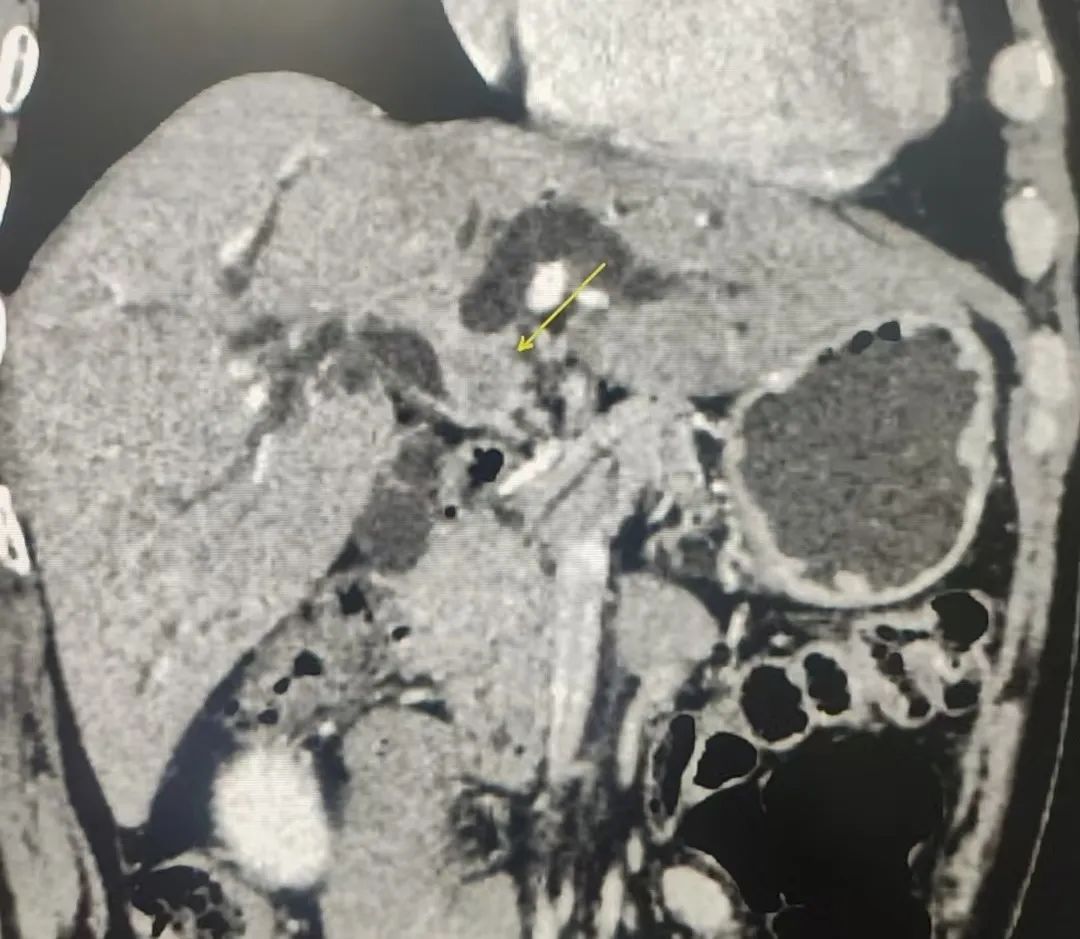

经过详细的体格检查,完善影像和实验室检查后,诊断其为:肝门胆管恶性肿瘤。普外科主任代坤介绍,肝门部胆管癌,就是长在肝门部胆管粘膜上皮的恶性肿瘤,因为位置特殊,起病隐匿,可能与胆管慢性炎症、胆管结石等有关。长期胆管炎会让胆管粘膜反复受损修复,胆管粘膜增生,可能发展成癌;有先天性胆管囊性扩张症、原发性硬化性胆管炎的人群,患癌的几率更高。值得警惕的是,患者早期症状可能不明显,随着肿瘤的生长,胆管被堵住,胆汁排不出去,黄疸会特别突出,出现皮肤、巩膜黄染,患者可能会有右上腹隐痛、胀痛,因为肿瘤影响消化,患者营养吸收不好消耗较大,会有吃不下饭、消瘦、没力气的表现。

基于术前影像,结合肿瘤实际累及程度、解剖变异以及切离极限点,外科团队邀请多科室开展MDT讨论,规划个体化精准手术方案。充分术前准备后,为其行“肝门部胆管癌根治术”。主刀手沉着冷静,仔细探查,精准分离,清扫组织,以雷霆之势完整切除病灶。“清点器械纱布,确认无误,关腹。”手术顺利,经过术后严格管理和精心护理,宗师傅很快康复出院,对东方医院集团广济医院普外科团队精湛的技术赞不绝口。

“根治术手术切除被认为是肝门部胆管癌最佳治疗方式。”代坤主任解释道:肝门部胆管癌根治术被称为“肝胆外科手术的天花板”。需要精细的外科技术,是肝胆外科最具挑战性的技术领域。由于胆管的解剖结构特殊,肝门部胆管的肿瘤像长在大树干分叉甚至更高位置,胆管的主干在肝门部,但它的分叉在肝里面,想把这个位置的肿瘤切干净,需要对血管和胆管进行非常精细的解剖和保护,把胆管和血管分离到非常高的水平,尤其是保护好分叉非常细的血管,对肝功能恢复非常重要,有的可能需要联合肝叶切除。“宗师傅生病虽然不幸,但能够顺利进行肿瘤根治,对他的预后有着非常重要的意义,相信在我们医患共同的努力下,可以大大提高他的生活质量。”